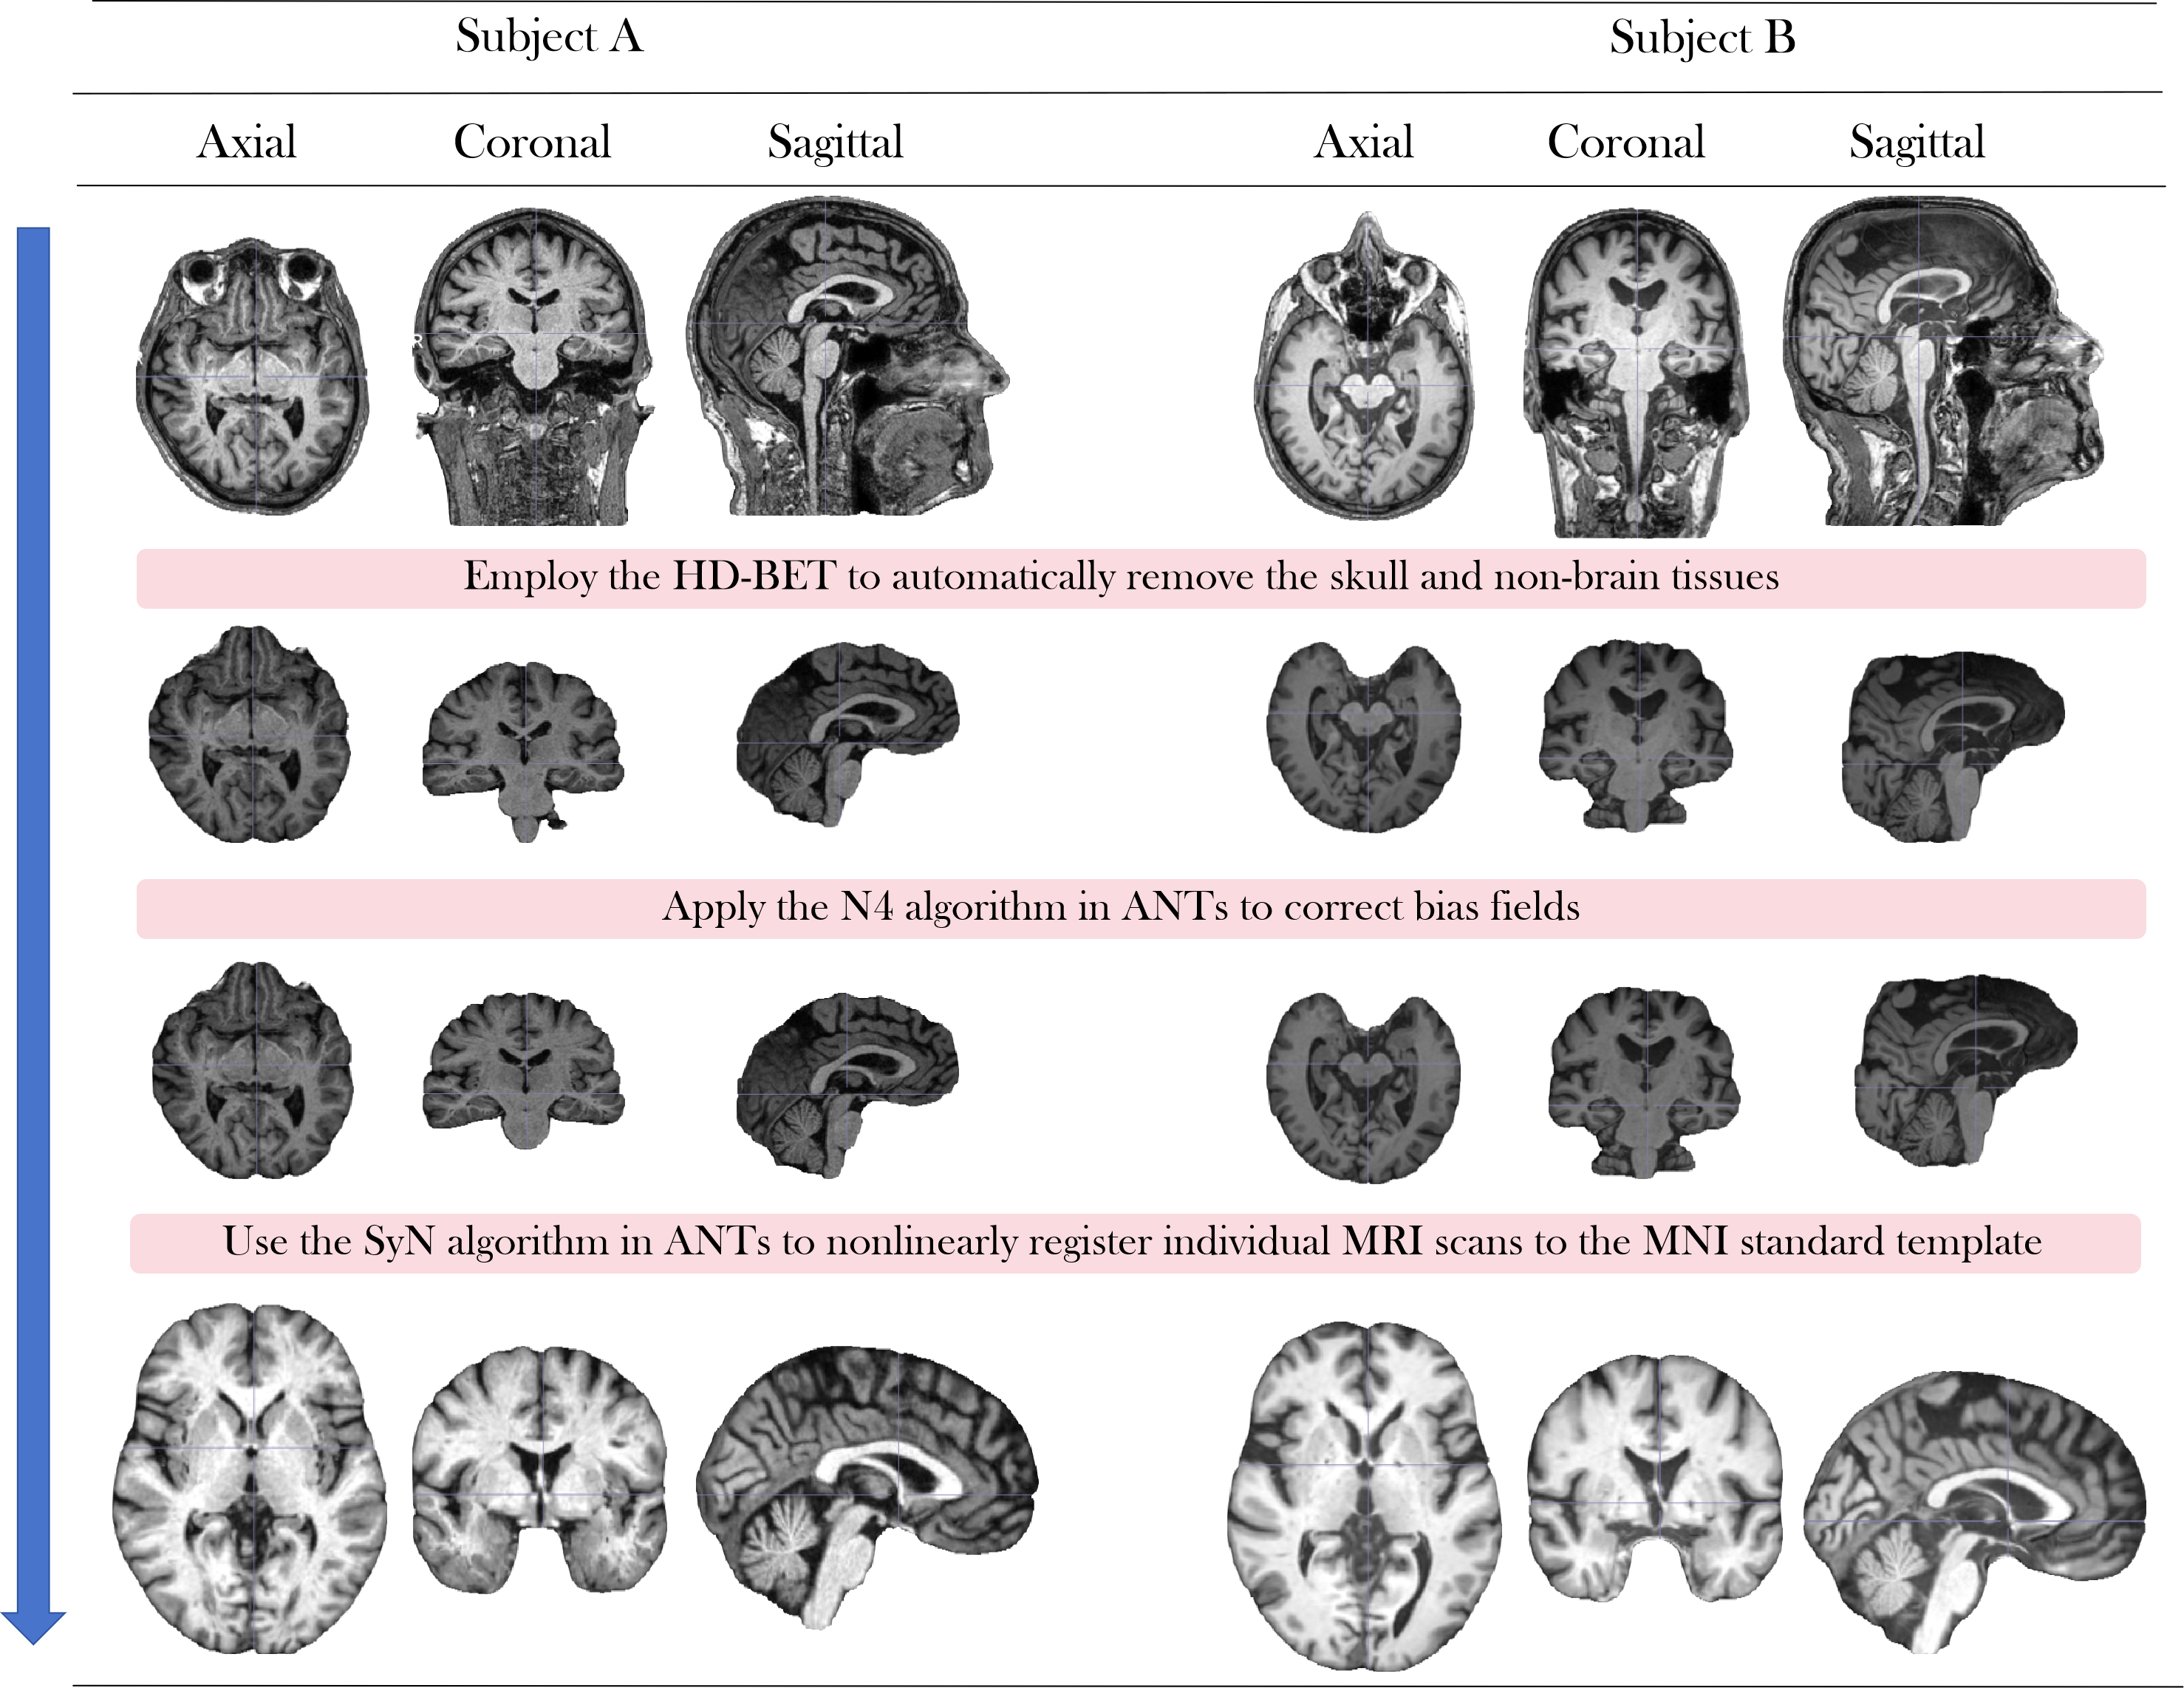

MRI-Processor (see Appendix F) integrates advanced MRI processing tools to standardize raw T1-weighted MRI scans, ensuring data quality and consistency while minimizing adverse effects caused by differences in scanner hardware and individual brain anatomy. It consists of three key steps: (1) Employ the HD-BET (Isensee et al., 2019) to automatically remove the skull and non-brain tissues, isolating the brain parenchyma and facilitating subsequent analysis. (2) Apply the Nonparametric Nonuniform intensity Normalization (N4) algorithm in ANTs (Avants et al., 2009) to correct bias fields, reducing intensity artifacts caused by magnetic field inhomogeneities during MRI acquisition and improving overall intensity uniformity. (3) Use the Symmetric Normalization (SyN) algorithm in ANTs to nonlinearly register individual MRI scans to the Montreal Neurological Institute (MNI) standard template, enabling consistent cross-subject comparison and group-level analysis.

The MRI-Processor includes three steps: (1) Employ the HD-BET (Isensee et al., 2019) to automatically remove the skull and non-brain tissues, isolating the brain parenchyma and facilitating subsequent analysis. (2) Apply the Nonparametric Nonuniform intensity Normalization (N4) algorithm in ANTs (Avants et al., 2009) to correct bias fields, reducing intensity artifacts caused by magnetic field inhomogeneities during MRI acquisition and improving overall intensity uniformity. (3) Use the Symmetric Normalization (SyN) algorithm in ANTs to nonlinearly register individual MRI scans to the Montreal Neurological Institute (MNI) standard template, enabling consistent cross-subject comparison and group-level analysis. The flowchart is shown in Fig. 8, and the pseudo code is listed in Algorithm 1.